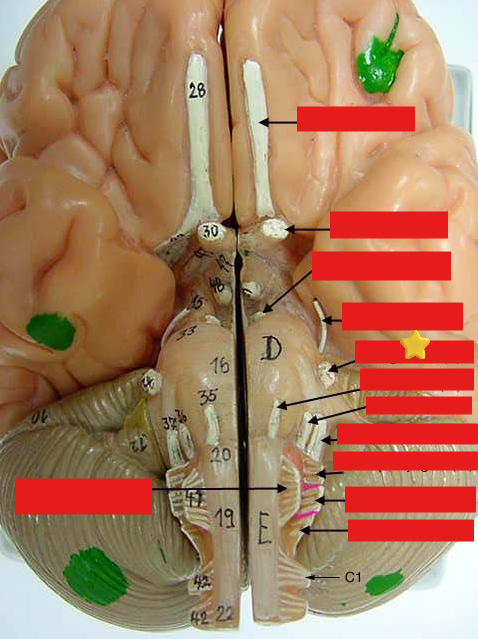

cranial nerves

12 Terms

1

olfactory

2

optic

3

oculomotor

4

trochlear

5

trigeminal

6

abucens

New cards

7

facial

8

vestibulocochlear

New cards

9

glossopharyngeal

New cards

10

vagus

New cards

11

accessory

New cards

12

hypoglossal

New cards